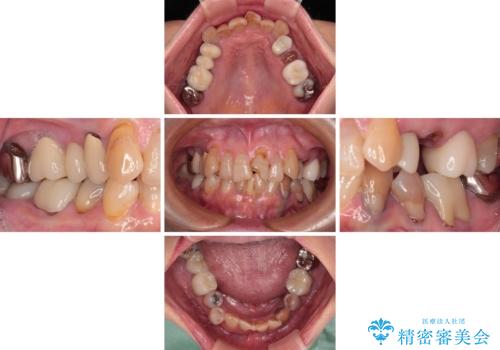

長年気になっていた前歯 矯正治療と補綴治療による審美歯科治療

デコボコが強いため、ブリッジや残根となっている部分のスペースを利用して歯列を整え、変色や欠けている歯をオールセラミッククラウンによる補綴治療を行うこととしました。

歯肉移植などによる前歯部の歯肉ライン改善を提案しましたが、口を開けたときにほとんど見えないので気にならないとのことで、特に処置を行うことなく補綴治療を行いました。